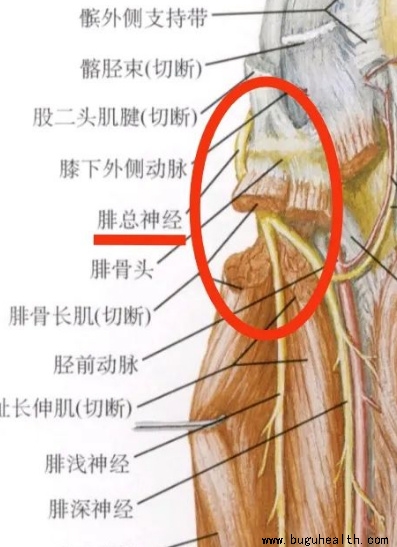

- 布骨医学科普:神奇的人体“开关”-周围神经卡压综合征! BuGuRMC布骨康复医疗中心 ,2023-04-23

- 在我们的人体,也存在着很多类似于空气开关作用的部位。脊髓是人体的中枢神经,它里面分出来很多条神经根,每根神经根控制的部位都不一样,相当于是配电箱里面分出来到各个房间不同的电线。.....